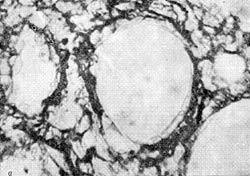

Соединительнотканный каркас легочной ткани новорожденных крыс

Соединительнотканный каркас легочной ткани новорожденных крыс:

а — контроль;

б — асфиксия на 20-й день внутриутробного развития. Импрегнация по методу Гомори. Х40Х7.